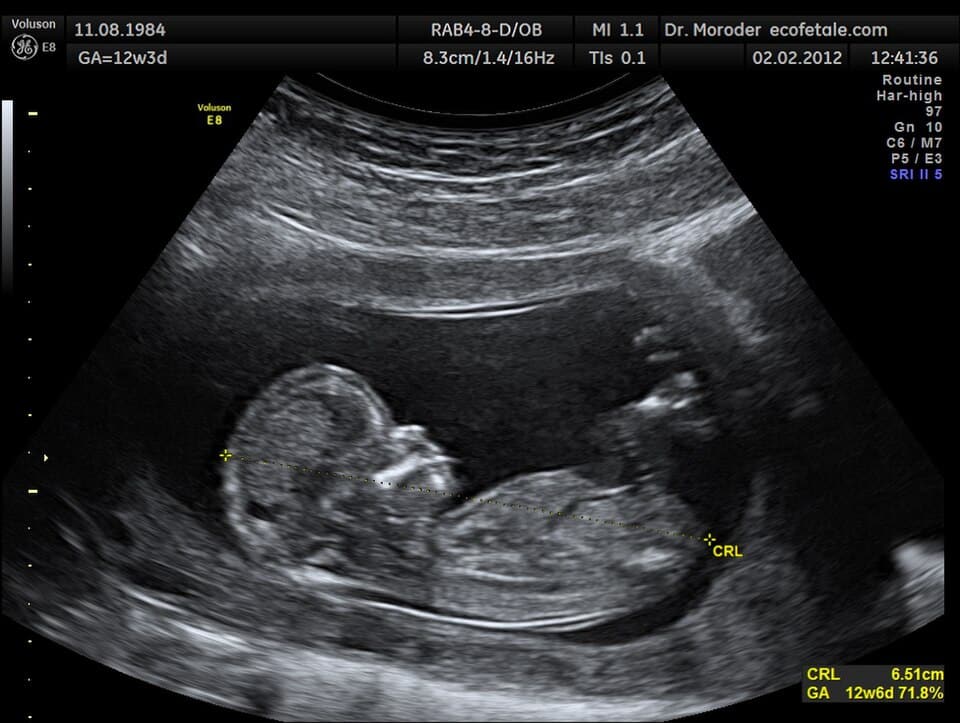

During the pregnancy test, Jessa revealed that she did not have a support system, and this pregnancy was truly unexpected and even unwanted. Her age already put her in the “high risk” category, and she wasn’t sure she could start over with a baby at her age. She was obviously scared and overwhelmed, and our staff met her where she was at. Jessa went back for her ultrasound, and her daughter joined her in the small, intimate room. In the quiet, low light, while our Nurse Manager performed the abdominal scan and our Client Services Director kept the mood light, the screen on the wall not only revealed that Jessa was further along than she thought, but she was carrying two babies.

Near the end of her pregnancy, Jessa and Josie found their way back to The Care Center. In the most casual way possible, Jessa shared with our staff that not only was she near the end of her pregnancy, she had decided that she would parent her babies. She decided with the support of The Care Center, Josie, and the rest of her family, the best thing for her daughters were to be raised by their mother. She beamed with joy and pride as she shared with us the names of her girls and showed us the most recent ultrasound images. Vivian and Violet were set to be born in just a few weeks. She told us she could never have carried the pregnancy or decided to parent the babies without the love and guidance she found at The Care Center. She cried with us, prayed with us, and allowed us to hug her neck. Her daughter even gave us a hug.